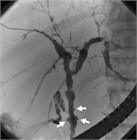

1. PSCとIgG4関連硬化性胆管炎との鑑別診断のためにERCPなどの直接胆管造影を行うことが推奨される(推奨度2、OJ)

1. PSCの診断のためにMRCPを行うことは強く推奨される(推奨度1、RSJG)